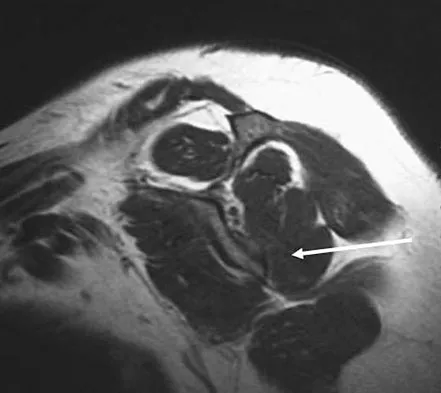

What structure is located at the tip of the arrow in Figure 18?

Explanation